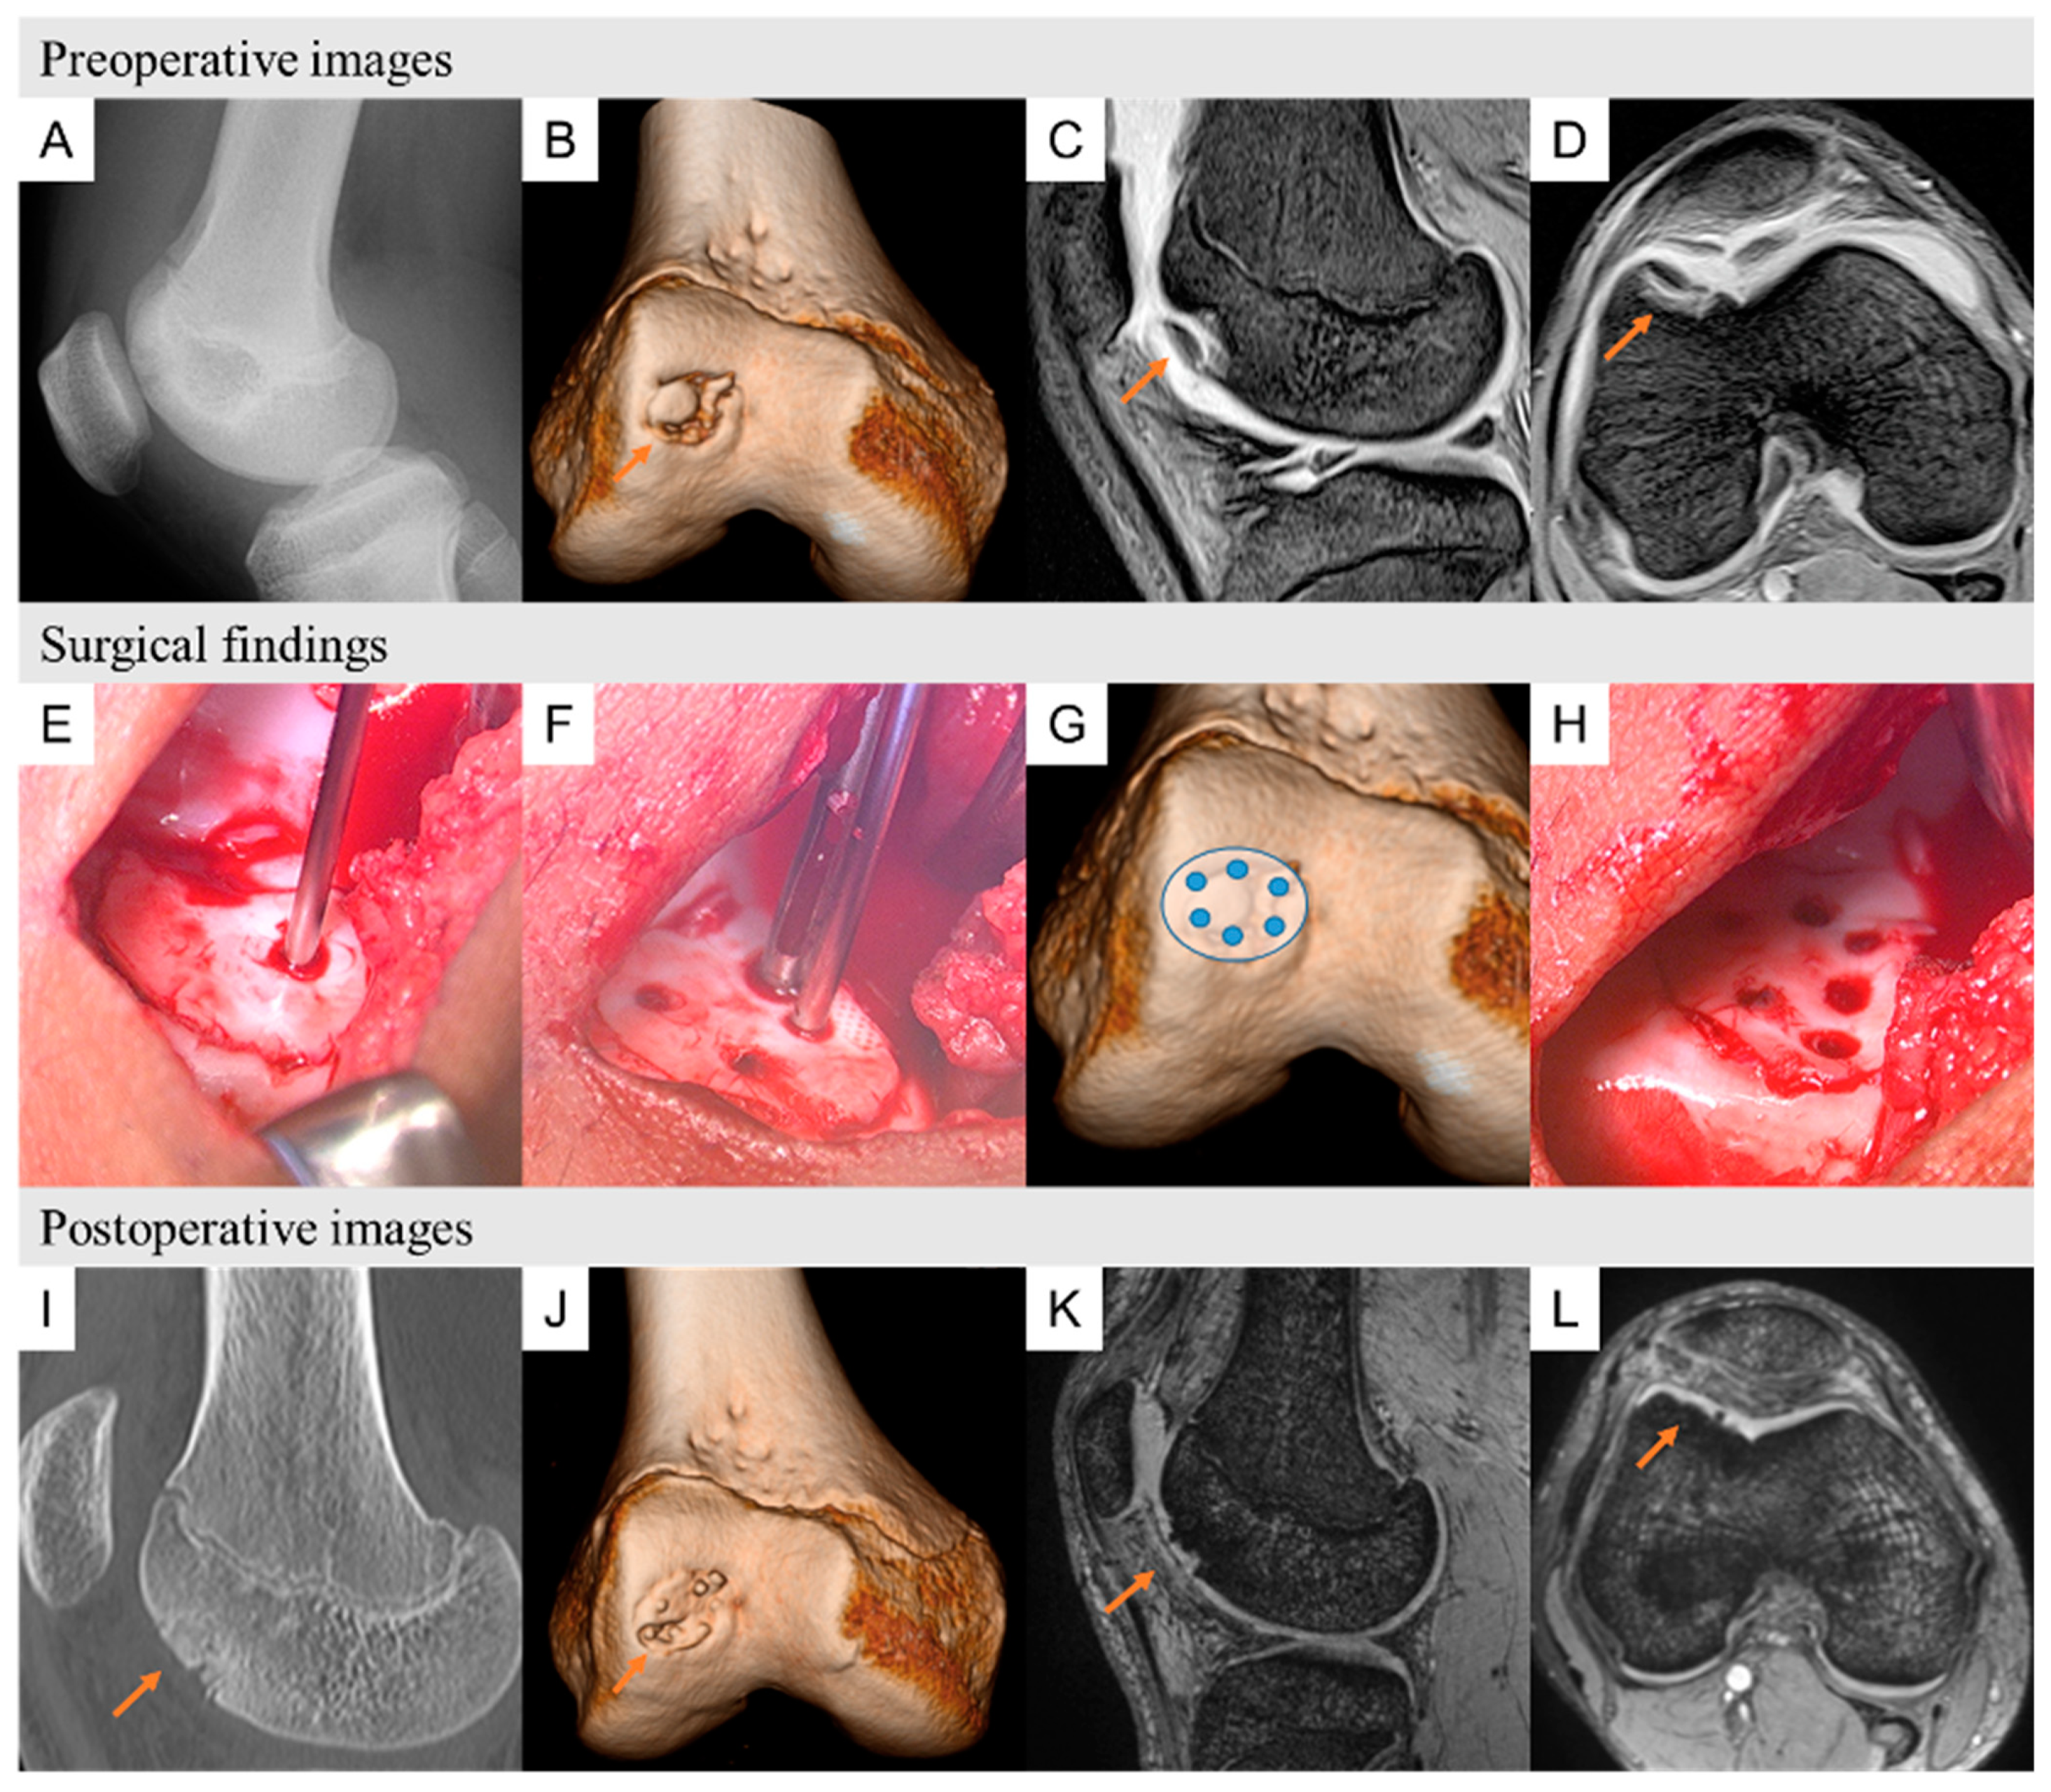

3.5. Case Presentation